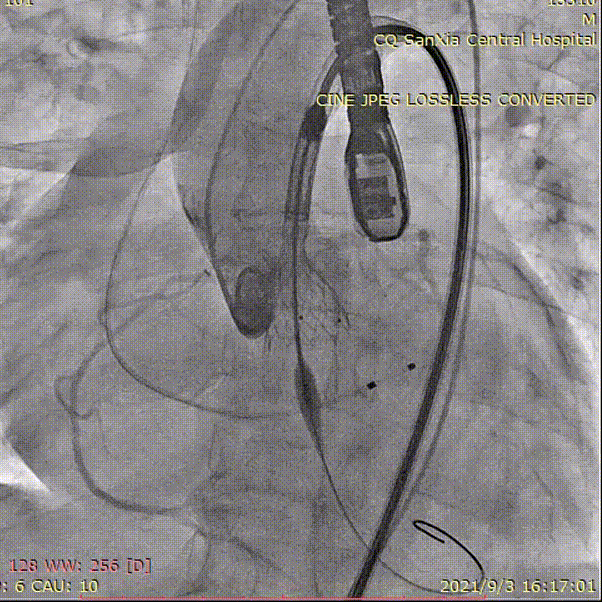

植入L23瓣膜定位,进行高位释放

造影评估

吴中杰老师对这台手术进行了总结:本院这台手术过程复杂,但结果是令人满意的。该患者主动脉瓣极重度钙化,且延续广泛,瓣上限制区域重,伴有全心增大、心肌薄、EF值低,手术风险和难度极高。因此对瓣膜的大小、释放位置有较高的要求,否则发生重度瓣周漏的风险较高。

对于这个病例我们经过术前讨论,预估到了术中可能出现的风险,并做出了完善的应对措施,而且采用启明的VenusA—Plus瓣膜支架,具有可回收功能,也保障手术能达到最佳效果,总体来说通过术前完善的准备和术中流畅的配合,手术是非常成功的。